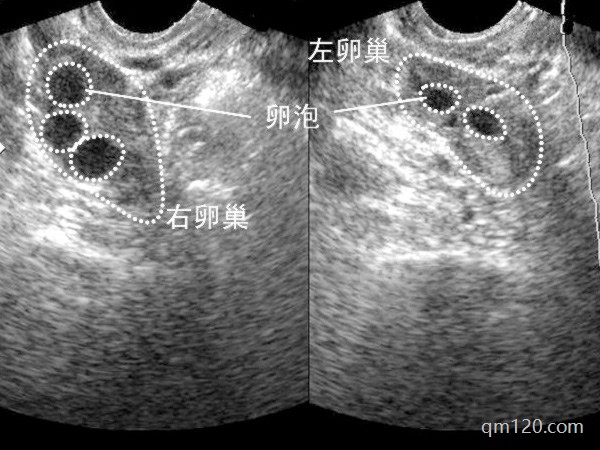

多囊試管促排卵泡質(zhì)量不好,卵泡太多怎么辦?可以針對性調(diào)整促排方案,以獲得更高質(zhì)量的卵子。接下來我們將詳細探討多囊卵巢綜合征(PCOS)患者在試管嬰兒促排卵過程中...

試管促排可以幫助誘導多個卵泡的發(fā)育,并獲得理想數(shù)量的成熟卵子,為隨后的胚胎形成和移植做準備。那么影響試管促排效果的因素有哪些?哪些因素影響試管促排?1、心理因素...